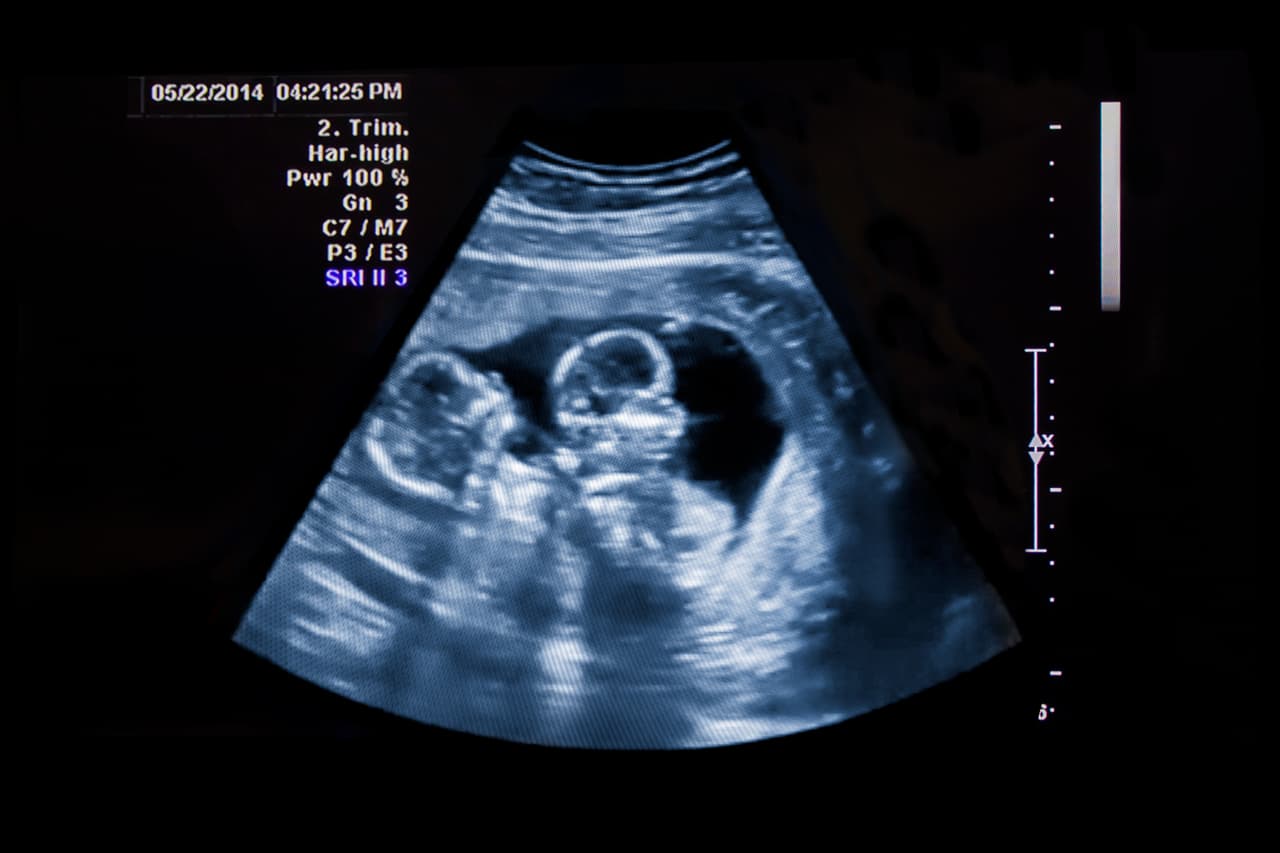

Ecografía

La entidad pediátrica Kids Health sugiere realizar una ecografía en el primer trimestre. Se trata de un estudio muy seguro e indoloro donde se puede ver la posición del bebé dentro del útero, a través de ondas sonoras.